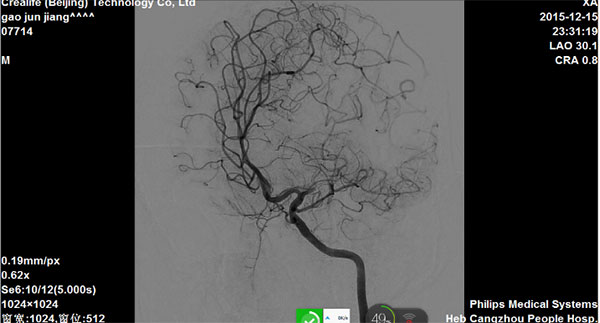

造影评估:急性左侧大脑中动脉闭塞

图1

图2